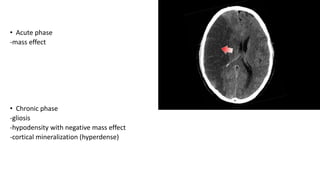

• Acute phase

-mass effect

-gliosis

-hypodensity with negative mass effect

-cortical mineralization (hyperdense)